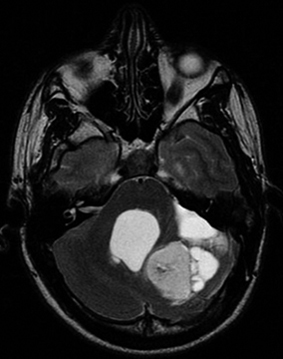

Les cheveux dans la tête

Dr Karima Mokhtari GHP Salpêtrière - paris

Clinique : femme âgée de 37 ans, sans antécédent, céphalées.

Imagerie IRM conventionnelle :

Large lésion cérébelleuse hémisphérique postéro-supérieure gauche en hypersignal T2. Intense prise de contraste après gadolinium ; zone centrale non rehaussée liée à la présence de calcifications.

Lésion kystique adossée latéralement à la lésion apparaissant